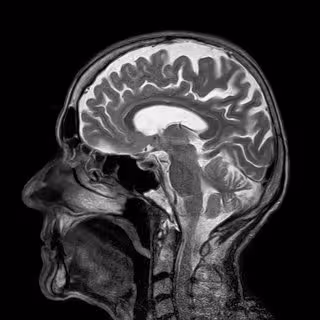

¿Qué causa las malformaciones cavernosas cerebrales?

Las malformaciones cavernosas cerebrales (CCM, por sus siglas en inglés) son grupos de vasos sanguíneos de paredes delgadas dilatados en el cerebro que pueden causar un derrame cerebral y convulsiones, pero es un misterio cómo se forman exactamente. Ahora, un equipo de la Facultad de Medicina Perelman en la Universidad de Pensilvania, Estados Unidos, ha descubierto el mecanismo molecular que subyace a esta enfermedad cerebrovascular común como detalla en un artículo publicado en la edición digital de 'Nature'.